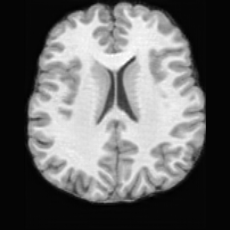

(a)PathologicalInput ImageSynthSR [18]Brain-ID [28]UNA [30]USBHealthyGround TruthRefer to captionRefer to captionRefer to captionRefer to captionRefer to captionRefer to captionRefer to captionRefer to captionRefer to captionRefer to captionRefer to captionRefer to captionRefer to captionRefer to captionRefer to captionRefer to captionRefer to captionRefer to captionRefer to captionRefer to captionRefer to captionRefer to captionRefer to captionRefer to caption(b)HealthyInput ImageConditionalLesion MaskUNA [30]USBRefer to captionRefer to captionRefer to captionRefer to captionRefer to captionRefer to captionRefer to captionRefer to captionRefer to captionRefer to captionRefer to captionRefer to captionRefer to captionRefer to captionRefer to captionRefer to caption

Figure 5: Comparison of bidirectional brain editing. (a) pathology-to-healthy, the circles and arrows highlight lesion regions and unsuccessful reconstructions; (b) healthy-to-pathology. Note that SynthSR and Brain-ID cannot perform healthy-to-pathology editing.

Pathology-to-Healthy Editing. Fig. 5 (a) presents comparison results on four input brain images with lesions of varying sizes, shapes, and densities. All competing models, although specialized for healthy brain image synthesis, struggle to reconstruct pathological regions, especially near lesion boundaries. In contrast, USB accurately reconstructs the corresponding healthy brain, even in challenging cases with large, high-density lesions where normal brain structures are almost completely obscured (last row). Tab. 2 provides a quantitative comparison for pathology-to-healthy editing, where USB achieves the best performance across all three datasets, demonstrating the effectiveness of its unified framework in reconstructing healthy brains from pathological inputs. Additional results are in Suppl. B.